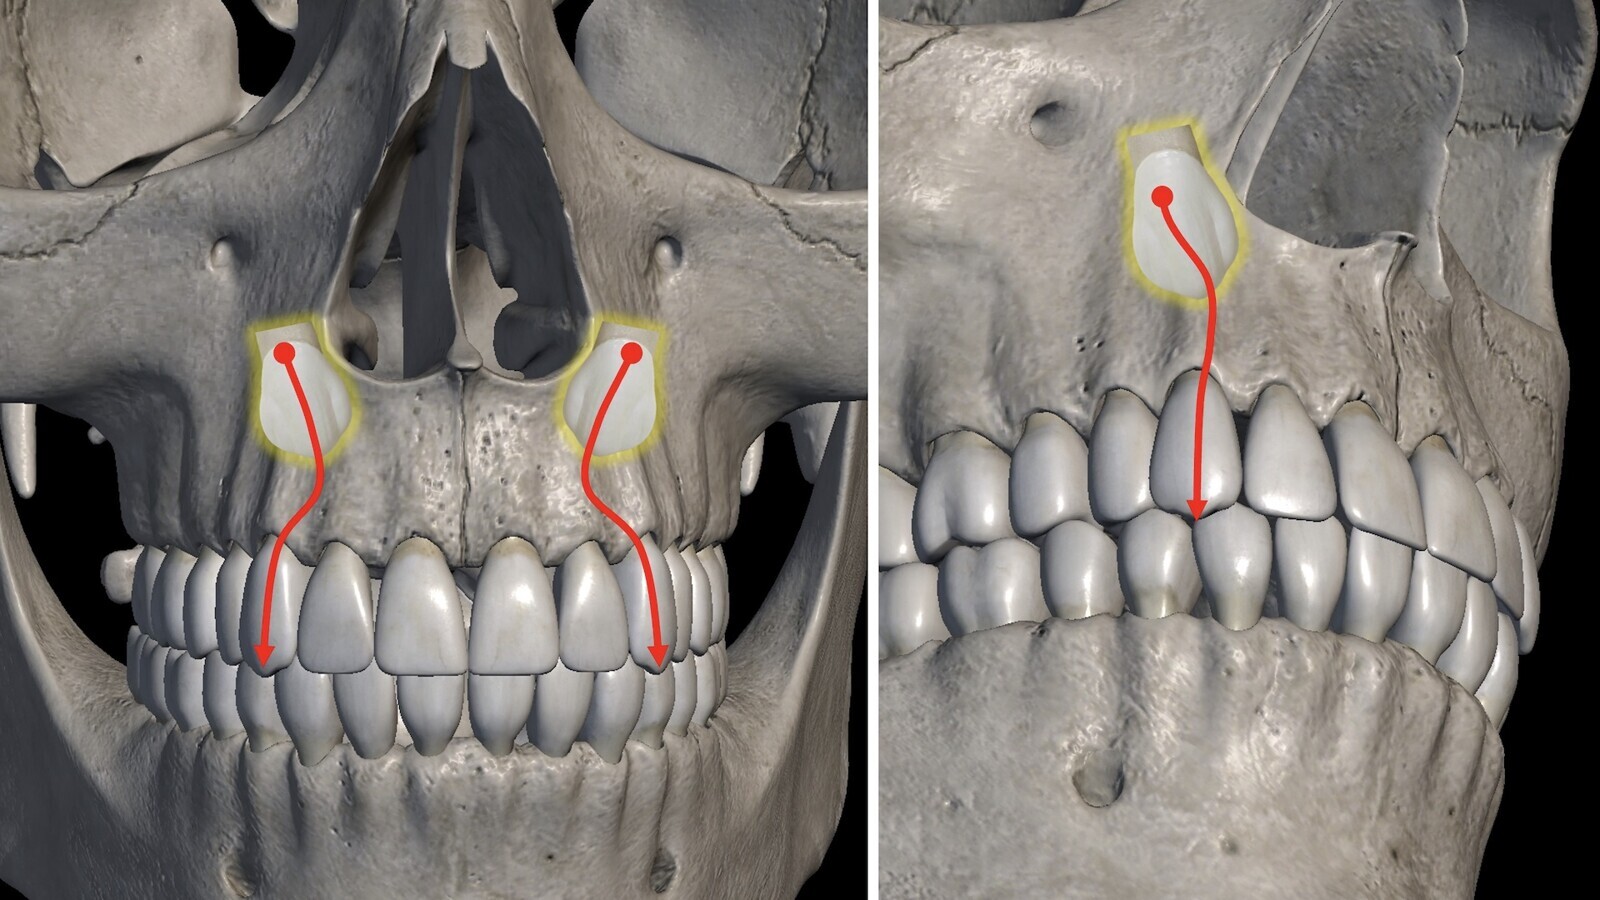

Diagrama que muestra que los cortes oclusales pueden tener una relación armoniosa de vecindad entre el canino con los incisivos y premolares o presentar signos de reabsorción externa de las raíces vecinas.

Los cortes transversales de los caninos nos orientan sobre su verdadera inclinación. Los cortes oclusales (figura 9) muestran la relación de vecindad del canino con los incisivos y premolares y si ésta es armoniosa (espacio de seguridad suficiente alrededor de la corona del canino) o presenta signos preocupantes de reabsorción externa de las raíces vecinas.

Figura 9. Los cortes oclusales muestran la relación de vecindad del canino con los incisivos y premolares y si ésta es armoniosa o presenta signos preocupantes de reabsorción externa de las raíces vecinas.

Sobre estos cortes oclusales también establecemos áreas poligonales de mejor (área I) a peor pronóstico (área III), según delimiten las zonas normales de emergencia canina o zonas muy alejadas. La suma de la angulación y la valoración objetiva de cada área ya nos va orientando sobre la mayor o menos dificultad del caso.